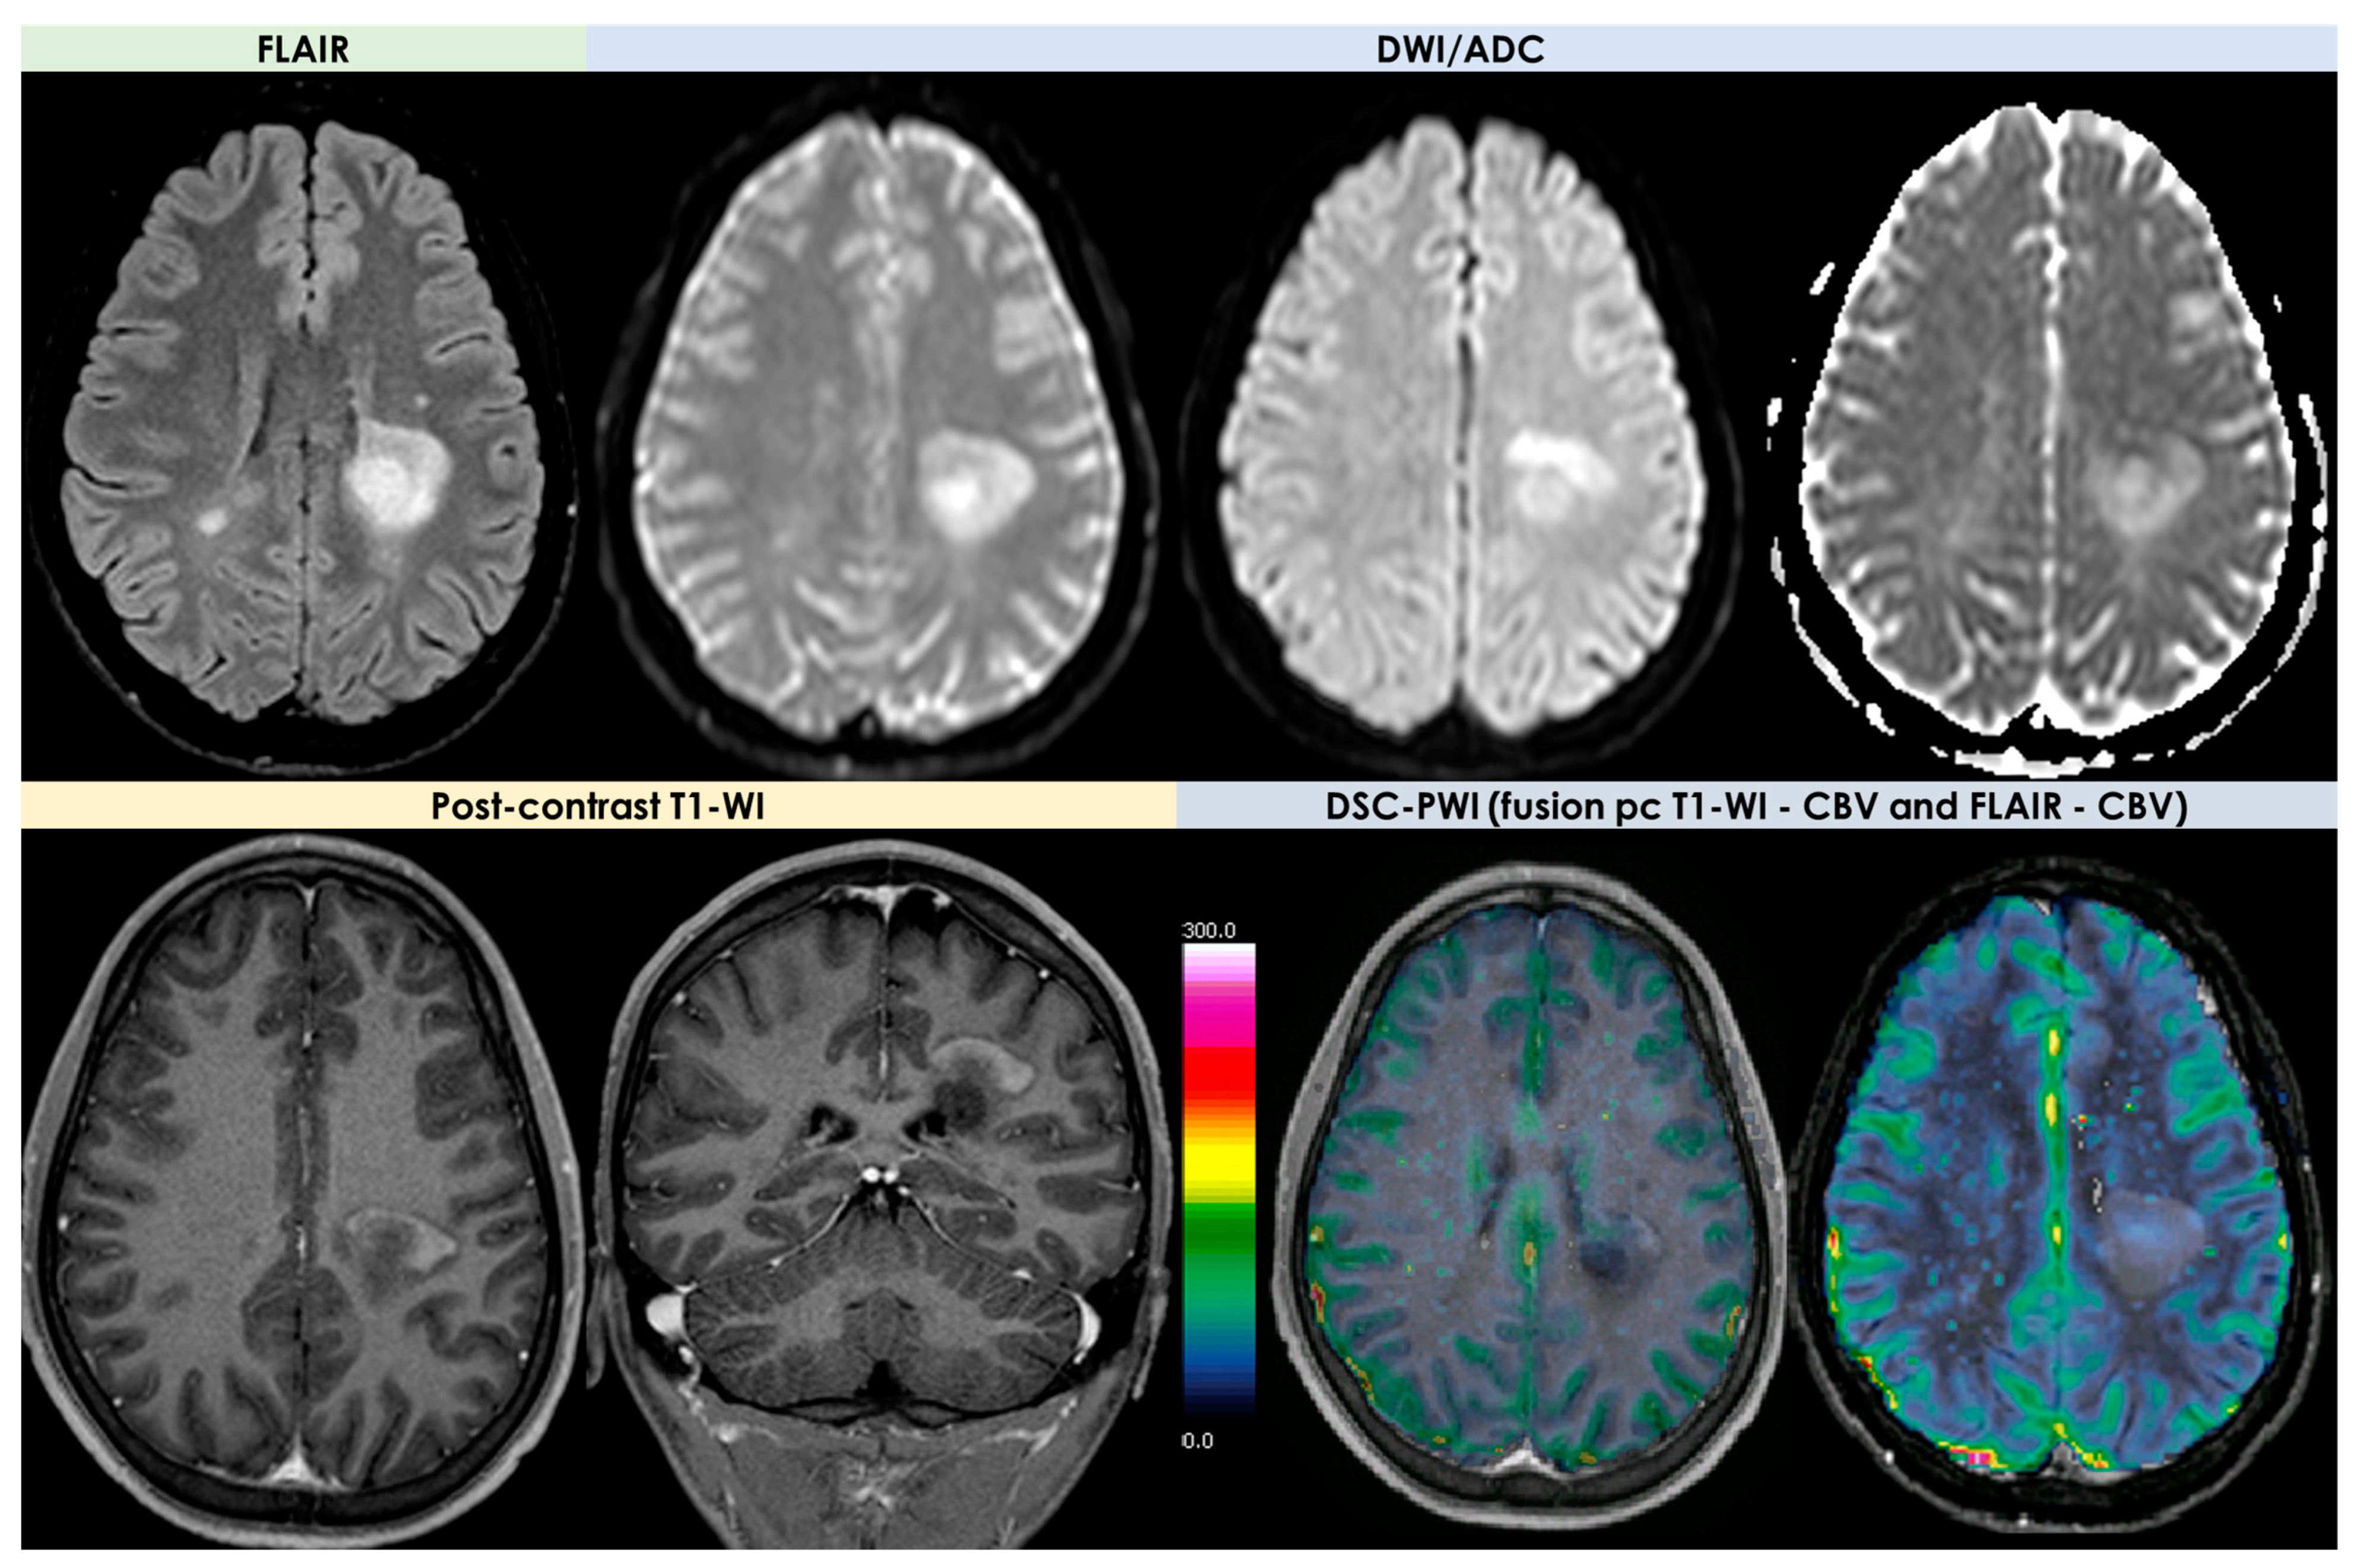

3.3. Tumefactive Demyelination Lesions

- -

- An open-ring or incomplete-rim enhancement;

- -

- A closed ring or complete rim enhancement;

- -

- A T2 hypointense rim;

- -

- An absent or mild mass effect;

- -

- Absent or mild perilesional edema.

| DWI/ADC | Hyperintense on DWI/hypointense on ADC maps Decreased FA values in lesions | High ADC values in center of lesion and relatively low ADC values in periphery of lesion Threshold for the minimum ADC value for distinguishing TDLs from PCNSL is 0.556 × 10−3 mm2/s | Hypointense in DWI and ADC | Hypointense on DWI and ADC | “Eccentric target sign” consisting of an eccentric nodule along the rim of an enhancing lesion on T1-WI ADC > 1.6 × 10−3 mm2/s suggestive of toxoplasmosis |

| DSC-MRI | rCBV lower than HGG Characteristic TIC | Few data with variable findings | rCBV usually higher than PCNSL, but variable findings | No data | rCBV lower than that in necrotic glioblastomas and metastases |

| Spectroscopy | Elevated lipid peaks and high Cho/Cr ratios | Increased Cho- peak Decreased NAA peak Increased Cho/NAA ratio | Elevated lipid peaks High Cho/Cr ratio | No data | No data |